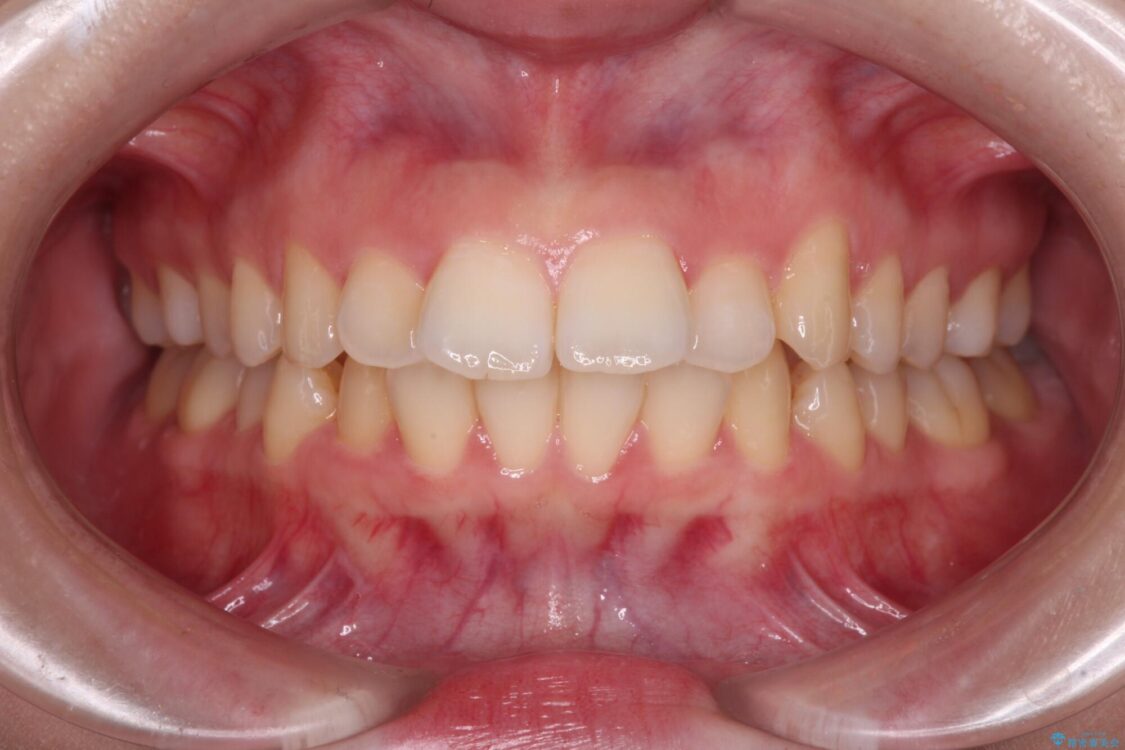

治療後

• 【モニター】口が閉じられない ワイヤー装置での抜歯矯正 治療後画像

治療後について

舌の突出癖があり、前歯の移動量も多くなるため、治療期間は長くなると予想されましたが、13ヶ月という予定の半分程度の期間で終えることができました。